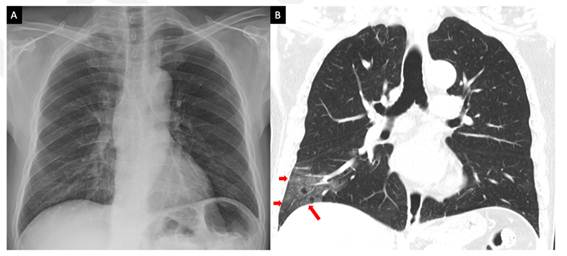

Sin duda, las imágenes médicas de los pulmones son una herramienta importante para ayudar a los especialistas, tanto en el manejo de pacientes con infecciones respiratorias agudas (IRA) como para confirmar otras enfermedades. En el caso de la COVID-19, los estudios confirman anormalidades visibles en la región pulmonar de algunos pacientes, sirviendo así como herramienta de decisión para los especialistas humanos. 14 Es importante tener en cuenta que existen pacientes con PCR positiva que no desarrollan signos o síntomas, por lo que es imposible diagnosticarlos mediante una imagen radiológica de sus pulmones. Las imágenes de TC presentan una mayor sensibilidad como método de diagnóstico y seguimiento en comparación con la CXR. Por ejemplo, se han descrito casos de COVID-19 con lesiones visibles en la TC, pero no visibles en la CXR.15 De hecho, uno de los principales hallazgos en las imágenes de TC de los pacientes con COVID-19 son las opacidades en vidrio esmerilado en las regiones periféricas de los lóbulos inferiores, las cuales en ocasiones no se pueden apreciar en las imágenes de CXR, como se muestra a continuación: (Fig. 1).

Sin embargo, en la mayoría de los centros de salud no se dispone del equipamiento necesario para adquirir la imagen de TC. Además, si existe un equipo de TC, no es posible dedicarlo exclusivamente a este diagnóstico en particular, dada la alta cantidad de pacientes infectados por COVID-19 existentes y la presión asistencial. Por otro lado, la CXR tiene la ventaja de estar disponible en la mayoría de los centros sanitarios. Su costo es mucho menor en comparación con la imagen de TC, y existe una modalidad portátil que evita que el paciente se mueva, minimizando la posibilidad de propagación del virus. Esto hace que se prefiera esta modalidad de imagen CXR, aunque sea menos sensible para el diagnóstico y el seguimiento del paciente.